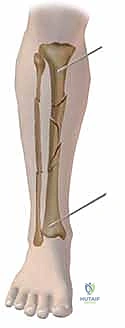

إصلاح انفصال أوتار الركبة الخلفية القريب: دليلك الشامل مع الأستاذ الدكتور محمد هطيف في صنعاء

اكتشف كل ما تحتاج معرفته عن علاج انفصال أوتار الركبة الخلفية القريب جراحياً مع الأستاذ الدكتور محمد هطيف في صنعاء، من التشخيص إلى التعافي ال…